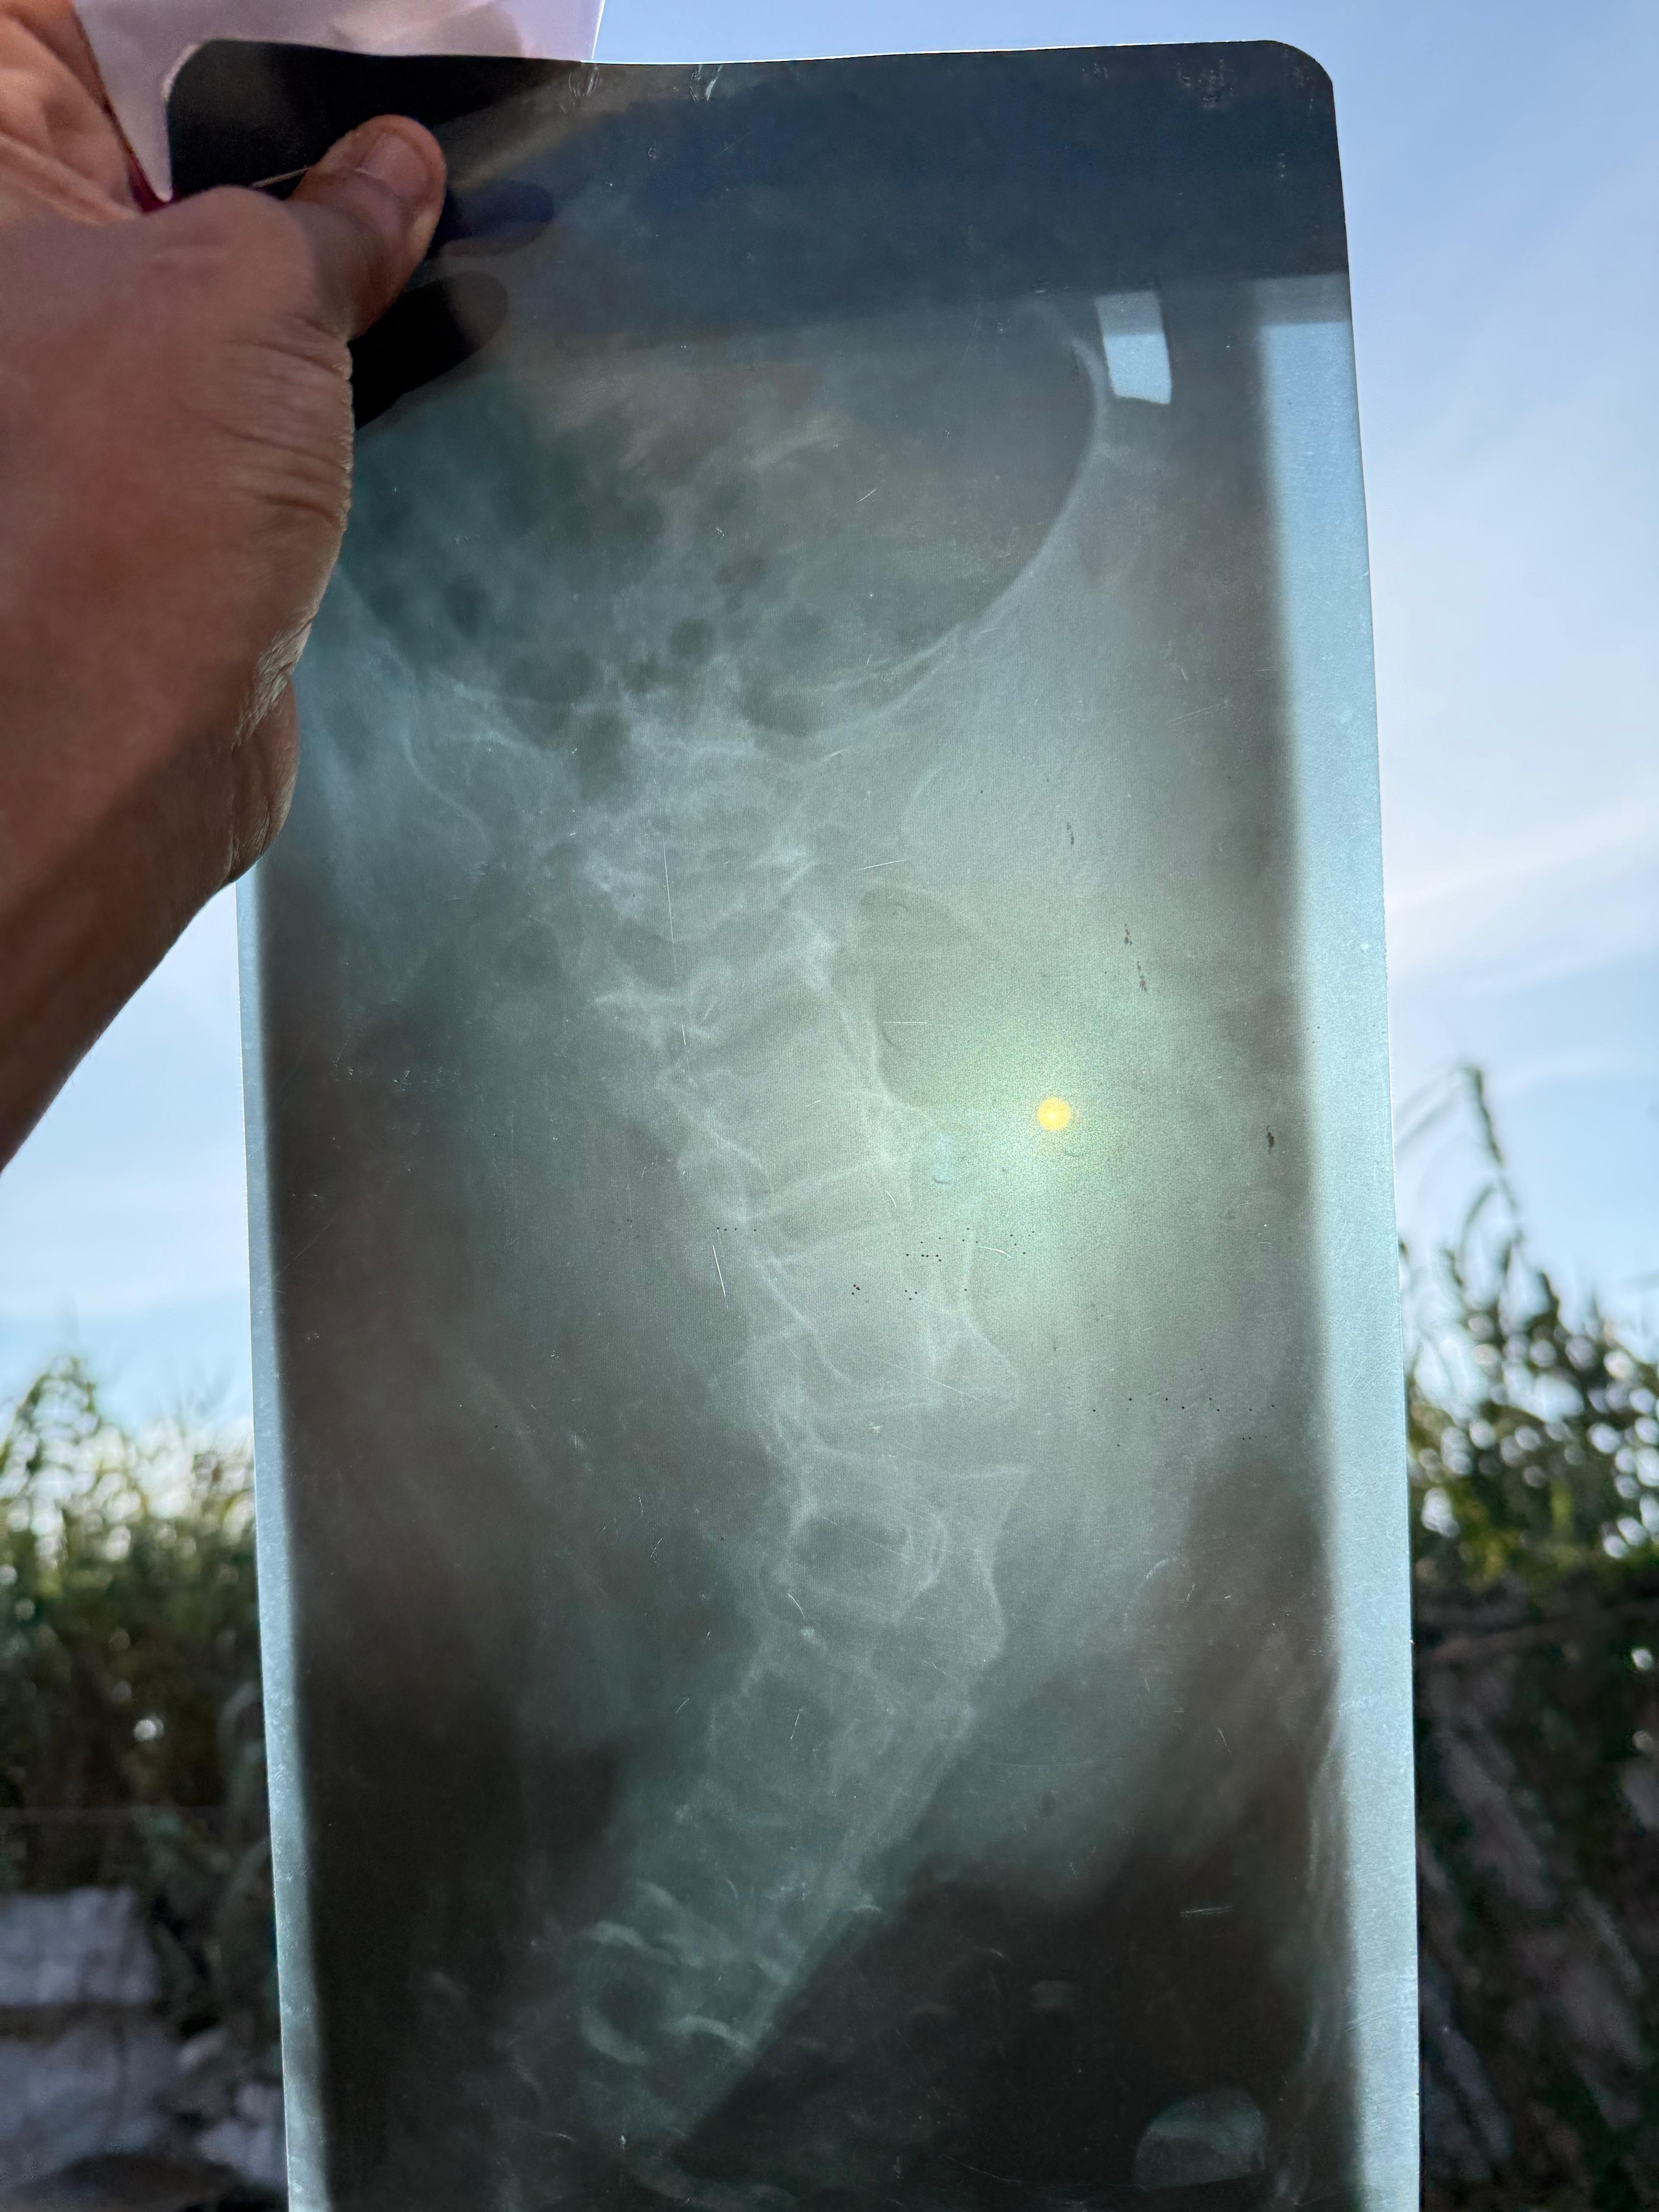

Hi, my name is Tzeghe Hintsa, and I am raising money for my niece, Shewit Hadish. She a 28-year-old living with a condition called Spinal Bifida, a spinal disorder that has caused severe physical and neurological problems. She has been unable to walk, eat or live a normal life, and unfortunately, she is unable to get the treatment she desperately needs in the country she lives in. It has taken months to get permission to leave the country for medical treatment and now that she has been cleared to leave, I am hoping to take her to Egypt, where she will undergo surgery to hopefully correct her spine and give her a second chance at life. I am raising money to help cover the cost of her surgery, any possible complications, recovery time in Egypt including her food, accommodation and medication. It will also go towards her travel back to Eritrea and any additional costs required by the embassy. Any help would be much appreciated and if you cannot donate, please spread the word as much as you can.